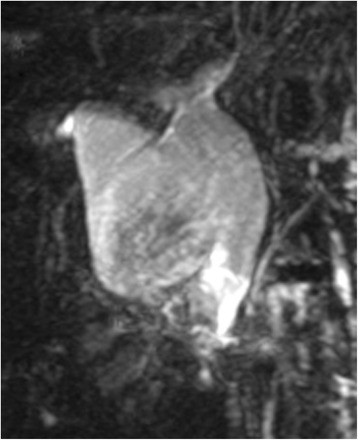

Abdominal ultrasonography revealed a cystic dilatation of the extrahepatic bile duct and two protruding tumors in the lumen of the dilated common bile duct (Fig. 1). Doppler ultrasound detected a blood flow signal within the tumor. Abdominal computed tomography (Fig. 2) demonstrated a cyst within the common bile duct measuring 7 cm in diameter and two enhanced tumors measuring 4 cm in diameter located in the inferior bile duct and middle bile duct. Magnetic resonance cholangiopancreatography (Fig. 3) clearly demonstrated a cystic dilatation of the extrahepatic bile duct (Todani’s CBD classification: type 4-A) [ref. 1]. Endoscopic retrograde cholangiopancreatography (Fig. 4) also demonstrated a cystic dilatation of the bile duct as well as the presence of two tumors. Biopsy of one of the tumors confirmed the presence of adenocarcinoma. Amylase, CA19-9, and carcinoembryonic antigen levels in the choledochal cyst were 54,722 IU/l, 230,853 U/ml, and 3.051 ng/ml, respectively.